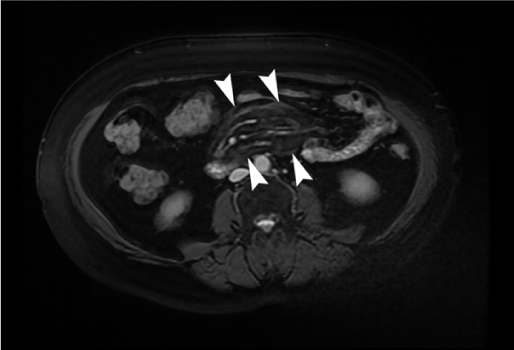

For further evaluation of the abdominal mass, MRI examination was performed. MRI showed a slightly inhomogeneous mass that predicted signal intensity changes on T1 and T2 weighted(W) sequences (Figures 2-5). All laboratory and radiologic examination results were compatible with MP. Oral steroid therapy was started. After 4 months, control MRI was performed done and presented that  the MR imaging  findings of MP were resolved.

Figure 5. On axial contrast–enhanced MR image, multiple mesenteric lymph nodes and preservation of fat around vessels and lymph nodes (fat ring sign, arrow) were seen in the hyperintense fatty mass.

In our study, MRI was performed to confirm the findings and MRI findings would be the main base for the follow-up.  Furthermore, MRI examination provided the differential diagnosis. MRI revealed an inhomogeneous fatty mass with changing signal intensity on T1 and T2W sequences. Like CT; Encapsulated, solitary, inhomogeneous fatty mass, without any vascular involvement, with no bowel wall invasion, and lymph nodes were the main MRI findings. MRI was more suitable for differential diagnosis and follow-up rather than primary diagnosis [12]. Ghanem et al. described the role of MRI in the diagnosis of the disease [12].